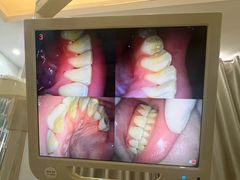

• 赫尔森口腔·牙齿种植修复

• -赫尔森口腔·牙齿种植修复

娜娜奇的 | 24-07-22